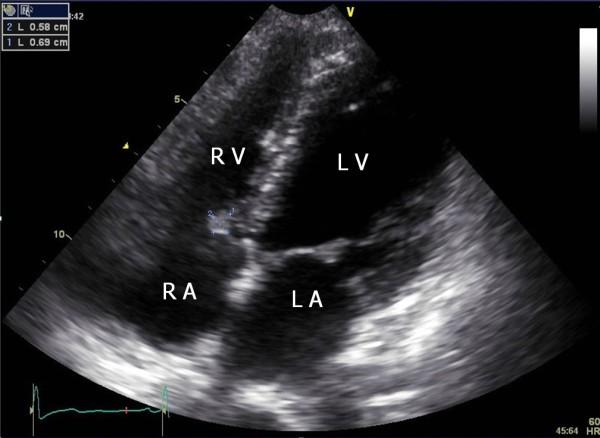

A 25-year-old woman with a history of kidney transplantation for lupus nephritis was referred for the evaluation and management of a mass incidentally found on echocardiography. An oval and pedunculated mass attached to the tricuspid valve was managed with nonsurgical treatment. No symptoms and complications attributable to the mass developed. Three years later, the size of the mass decreased. Here we report the case of a probable cardiac papillary fibroelastoma (PFE), a mobile mass, with a stalk on the septal leaflet of the tricuspid valve that was managed for three years without surgical treatment.